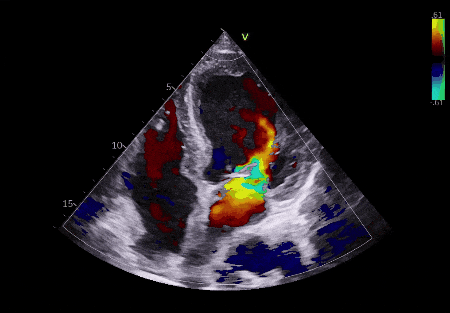

▲术后超声

原本严重的主动脉瓣反流瞬间消失,心脏的血流动力学立刻恢复正常。整个手术仅用时1小时,患者全程生命体征平稳,无任何并发症。